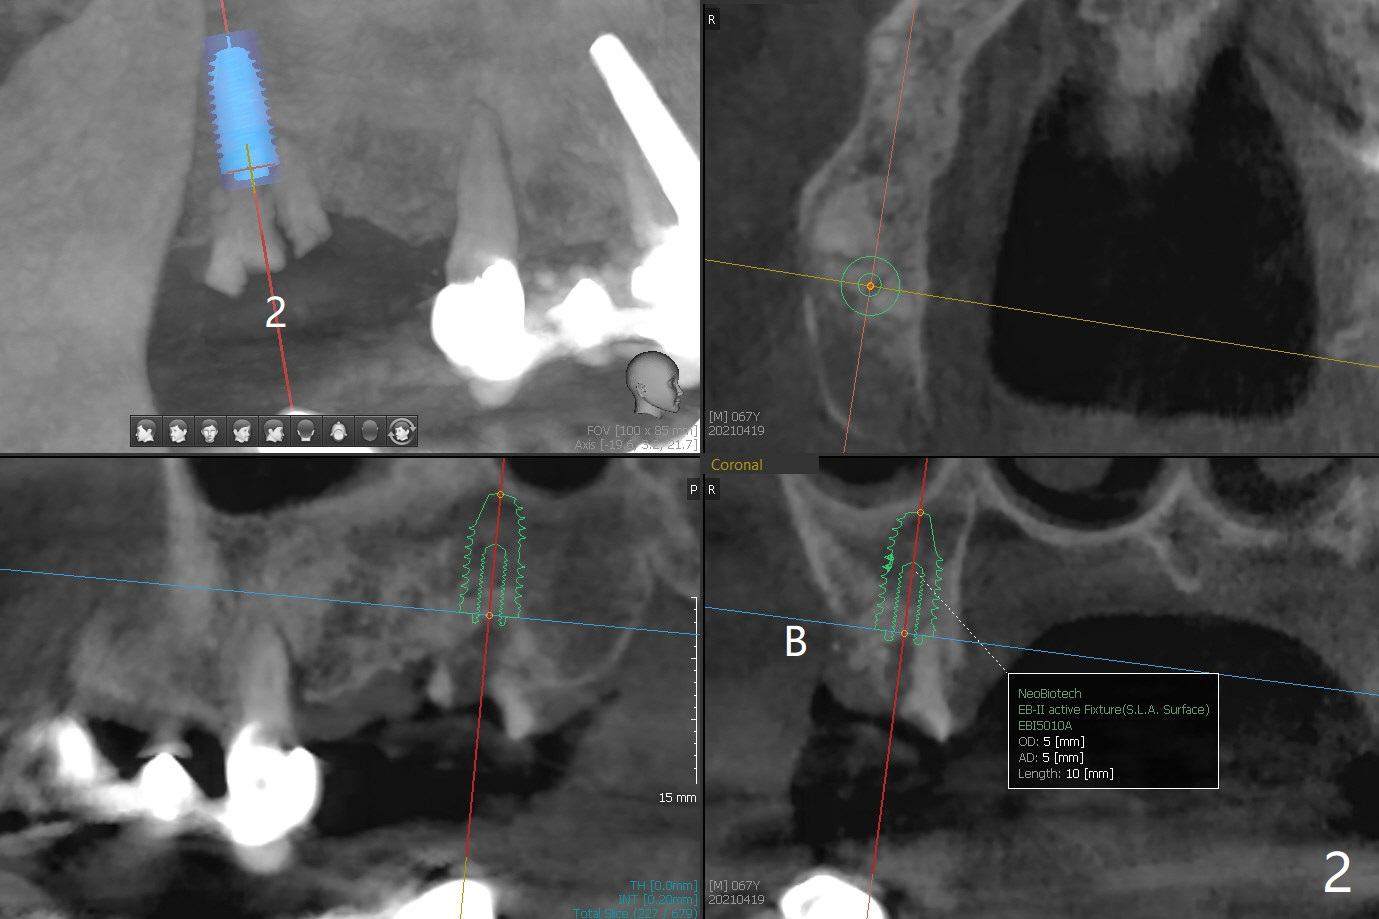

67岁男14号牙植牙牙冠粘固后两年回来处理右上(2-6)桥问题,撤除2,3单位(图一),准备种植(图二,三),3号牙牙槽嵴比较窄(图三),勉强植入4x10毫米植体,我想借助导板和它的钻头进行骨扩张,这样可以植入稍微大植体,例如4.5毫米。能不能最细钻头顺转,而再粗的钻头倒旋达到扩张目的?3号牙牙槽骨平均密度650单位。